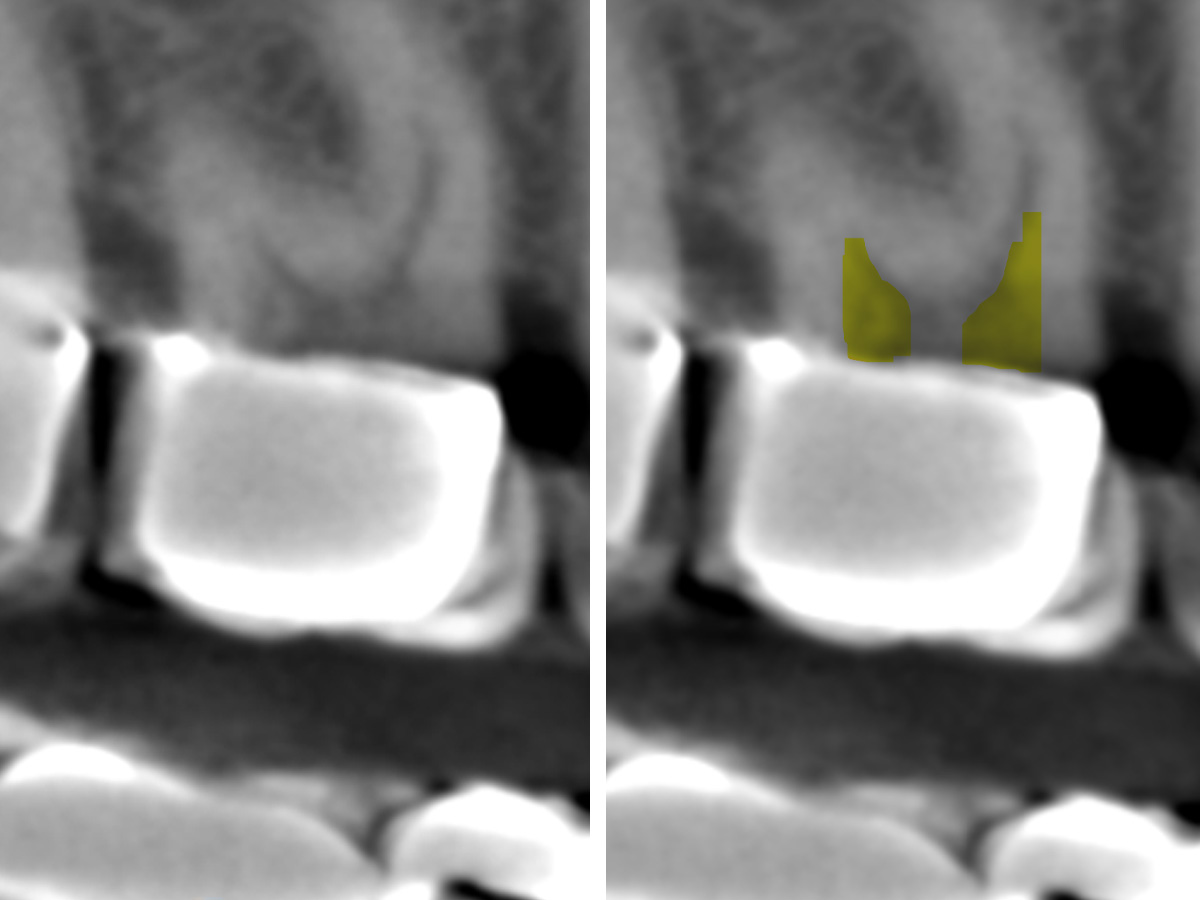

Abbildung 1

Röntgenologisch (Einzelbild 16-17) sind zwei Einzelkronen erkennbar. Keine zusätzliche diagnostische Information.

Abbildung 2

Nach der DVT-Untersuchung (Kodak 9000 3D, Auflösung 0,076 mm) bestätigte sich eine apikale Parodontitis an Zahn 16 palatinal. Eine Wurzelkanalbehandlung an Zahn 16 ist indiziert.